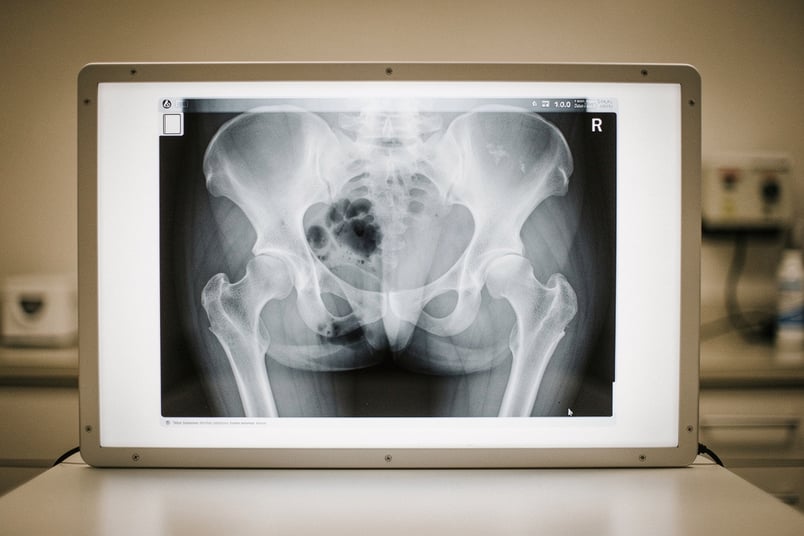

A bilateral condition is one that can affect both sides of the body — both knees, both hips, both eyes. This is one of the biggest hidden traps in pet insurance. Many insurers have a bilateral condition clause: if one side is pre-existing, they exclude BOTH sides. So if your dog tore its left ACL before coverage, the right ACL is also excluded — even though it's perfectly healthy.